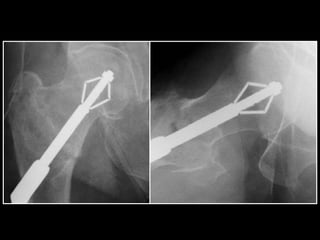

‘Tip-Apex’ fixation maintained

Best bone quality & trabecular lines

Snug fit in drill-hole

Not so snug